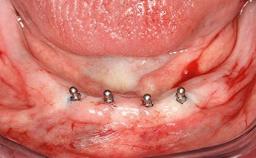

A 93-year-old female patient presented in September 2010 with an enlarged swelling on the lingual side of her lower incisors. At the time, she was essentially healthy, except for reduced vision due to bilateral age-related macular degeneration. She had been a heavy smoker (about 30 cigarettes a day) for the past 20 years after becoming a widow. The patient lived at home by herself, with full-time domestic support. An extraoral examination revealed nothing adverse. Intraoral plaque control was anything but ideal, and a soft-tissue tumescence was visible around the lingual aspect of 41–42. Because the nature of the lesion was not clear, a biopsy was carried out that revealed the inflammatory nature of the lesion. The panoramic radiograph showed six irregularly distributed mandibular implants supporting a full-arch prosthesis, with various degrees of interproximal peri-implant resorption. The periapical radiograph revealed interproximal bone resorption mesially and distally to implant 41.